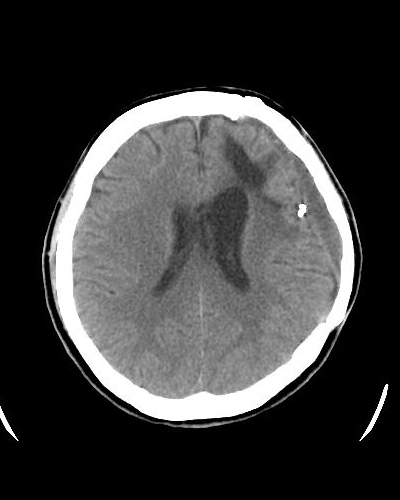

- 脳梗塞

脳梗塞の血栓回収療法は、カテーテルで詰まった血のかたまりを取り除き、途絶えた脳の血流を早く再開させることで、重い後遺症や命の危険を減らす治療です。 開頭手術を行わず、足の付け根などから細い管を挿入する低侵襲な方法で、薬の点滴治療(tPA静注)と組み合わせることで、重い麻痺や言語障害などの後遺症を大きく減らせる可能性があります。当院では24時間体制で救急対応しており、専門医が迅速に治療を行います。

血栓回収術前(脳底動脈閉塞)

血栓回収術後